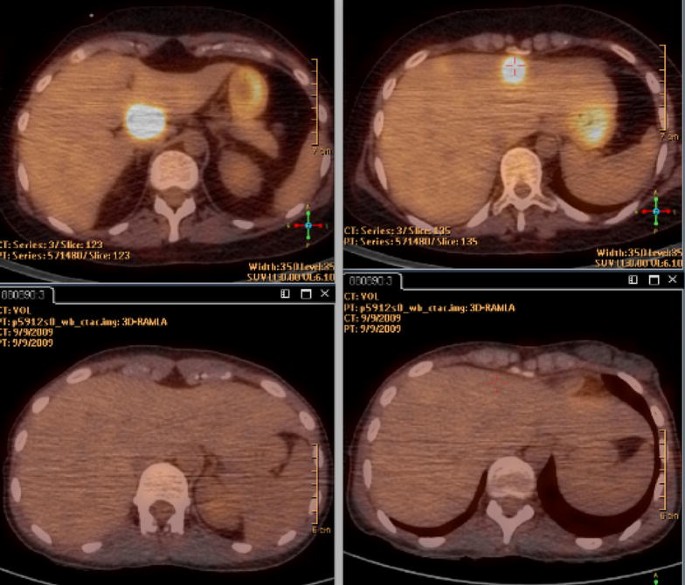

The evolution was firstly favorable but 2 months later neurologicals signs reappeared and a new MRI concluded an increase of the mass, 41 × 24 versus 32 × 18 mm at the last control). PET/CT has not found any systemic lesion. A second line of chemotherapy with ifosfamide (2000 mg/m2), coupled with radiotherapy was made with success but <1 month after the beginning of the treatment, the patient again presented with paresis of the right upper limb while the fronto-parietal brain injury declined. MRI of the whole spinal cord found an extending lesion from C2 to C4 (Fig. 2), which in this context, is suggestive of recurrence of lymphoma whereas no meningeal infiltration was found on lumbar puncture. It was decided to combine radiotherapy with temozolomide. PET/CT performed in conjunction confirmed the relapse, moreover, multiple liver lesions were found (Fig. 3). Liver biopsy found a recurrence of diffuse large B-cell lymphoma expressing the CD20 antigen with a high proliferation index (Ki67 in 95 % of tumor cells). Chemotherapy according to the protocol of the European Group of Lymphomas of the Adult (GELA): R-ACBVP (rituximab 375 mg/m2—adriamycin 75 mg/m2—cyclophosphamide 1200 mg/m2—vindesine 2 mg/m2—bleomycin 10 mg/m2—prednisone 60 mg/m2) was started but the patient died at the end of the second cycle of treatment.

In this case, the regular performance of PET/CT whole body has enabled us not only to confirm the nature of the primitive brain lymphoma (excluding when diagnosing any systemic involvement) but also it relapse in the cervical spine and liver. PET/CT has a resolution more efficient than conventional CT for the assessment of brain lymphoma as systemic lesions are identified much earlier (Mohil et al. 2008).